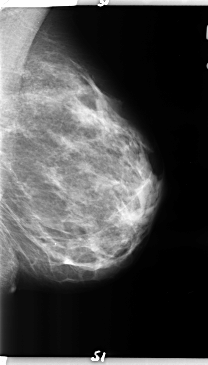

ics_version 1.0 filename B-3157-1 DATE_OF_STUDY 9 6 1997 PATIENT_AGE 42 FILM FILM_TYPE REGULAR DENSITY 2 DATE_DIGITIZED 5 5 1998 DIGITIZER LUMISYS LASER SEQUENCE LEFT_CC LINES 4720 PIXELS_PER_LINE 2928 BITS_PER_PIXEL 12 RESOLUTION 50 NON_OVERLAY LEFT_MLO LINES 4736 PIXELS_PER_LINE 2704 BITS_PER_PIXEL 12 RESOLUTION 50 NON_OVERLAY RIGHT_CC LINES 4704 PIXELS_PER_LINE 2800 BITS_PER_PIXEL 12 RESOLUTION 50 OVERLAY RIGHT_MLO LINES 4672 PIXELS_PER_LINE 3032 BITS_PER_PIXEL 12 RESOLUTION 50 OVERLAY |